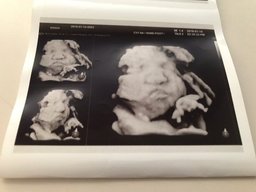

gimemi(25)•in #baby•2560 days ago31주3일 3D초음파 안녕하세요! @gimemi입니다. 오늘도 오랜만에 아가 얼굴을 보고 왔어요~ 28주부터는 2주에 한번씩 검사해야한다고 하더라구요! 이제 수원에서 이것저것 준비를 하고 아예 내려오느라 31주때 방문을 했어요. 저는 그 3주사이에 2키로나 뿔었네요...후 왜이럴까요 ㅠㅠ 흑흑 아가도 1.1...139$0.10gimemi(25)•in baby•2560 days ago31주3일 3D초음파 안녕하세요! @gimemi입니다. 오늘도 오랜만에 아가 얼굴을 보고 왔어요~ 28주부터는 2주에 한번씩 검사해야한다고 하더라구요! 이제 수원에서 이것저것 준비를 하고 아예 내려오느라 31주때 방문을 했어요. 저는 그 3주사이에 2키로나 뿔었네요...후 왜이럴까요 ㅠㅠ 흑흑 아가도 1.1...139$0.10

gimemi(25)•in #baby•2579 days ago28주5일! 탑동이 얼굴확인안녕하세요! @gimemi입니다. 다들 크리스마스 잘 보내셨나요? 벌써 28주 5일이에요.. 남은 날도 70일대로 접어들었죠.. 시간 진짜 빠르네요 ㅠㅠ 드디어 얼굴을 확인할때가 왔어요! 두근두근! 그러나 여전히 까칠한녀석 얼굴을 잘 보여주지 않더라구요 ㅠㅠ 양다리를 폴더로 얼굴까지 접...1410$0.09gimemi(25)•in baby•2579 days ago28주5일! 탑동이 얼굴확인안녕하세요! @gimemi입니다. 다들 크리스마스 잘 보내셨나요? 벌써 28주 5일이에요.. 남은 날도 70일대로 접어들었죠.. 시간 진짜 빠르네요 ㅠㅠ 드디어 얼굴을 확인할때가 왔어요! 두근두근! 그러나 여전히 까칠한녀석 얼굴을 잘 보여주지 않더라구요 ㅠㅠ 양다리를 폴 더로 얼굴까지 접...1410$0.09